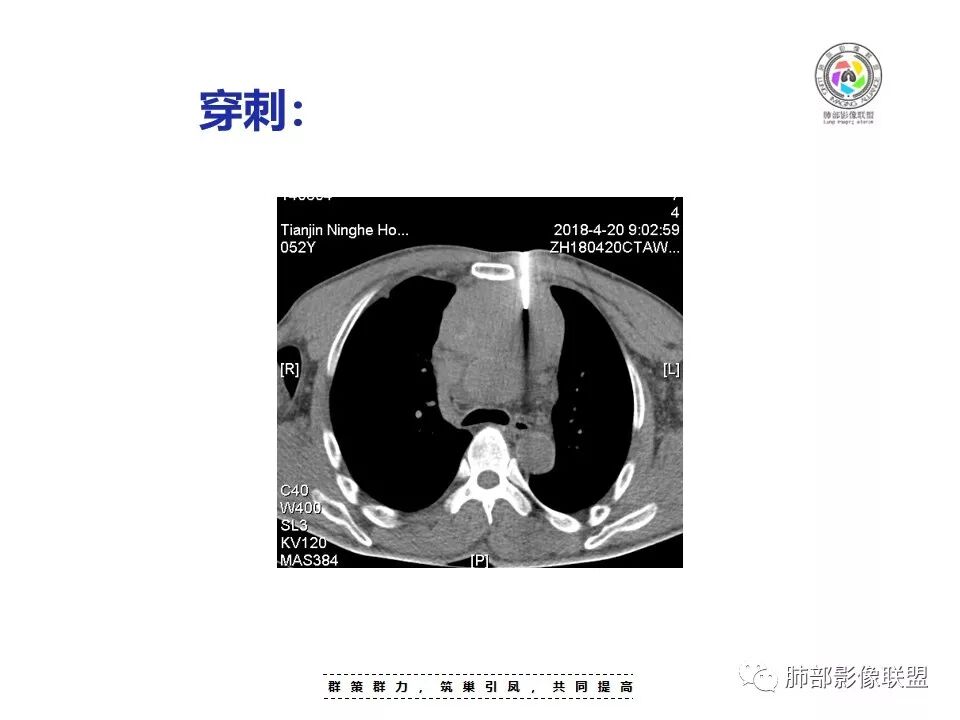

定位没问题:前纵隔。

较大,内有囊变、钙化。

南边:边界大部分清楚,有些地方毛糙。

上腔静脉如何?

心包如何?

大肿块,边缘不清,伴随肿大淋巴结,上腔静脉受侵犯——恶性

侵袭性胸腺瘤?胸腺癌?老年,钙化、肿大淋巴结,边缘侵犯、累及心包、侵犯上腔静脉——支持

患者前纵隔囊实性肿块,常规疾病普考虑胸腺瘤、胸腺癌、生殖细胞肿瘤、淋巴瘤和神经内分泌肿瘤,其中神经内分泌肿瘤中最常见的是类癌,患者的年龄不支持生殖细胞瘤,具体分析如下:

1.  病灶内实质性钙化,提示AB型以上胸腺瘤、胸腺癌或类癌,其中微钙化往往提示高危型胸腺瘤跟胸腺癌、类癌,同时也排除了淋巴瘤(淋巴瘤不会有钙化);